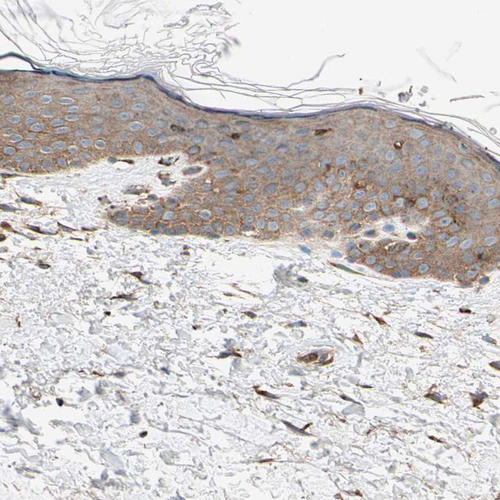

Immunohistochemical staining of human placenta shows strong granular cytoplasmic positivity in trophoblastic cells.